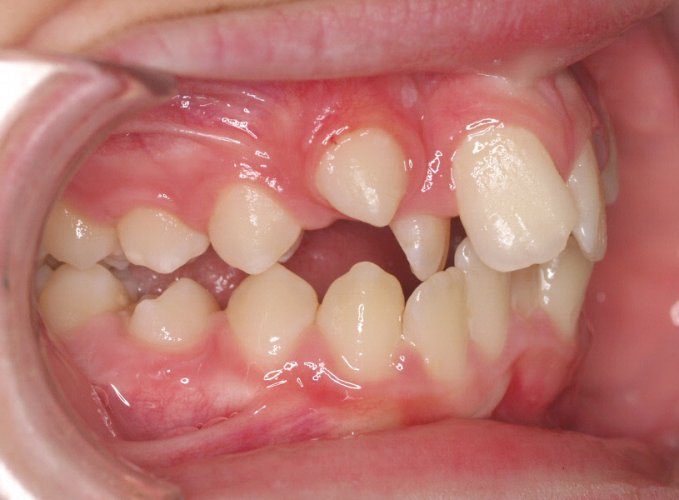

Un “diastema” es una separación extraordinariamente grande entre dos o más dientes. La mayoría de las veces, el diastema aparece entre los dos dientes delanteros superiores. Muchos niños tienen diastema cuando se les caen los dientes de leche, pero en la mayoría de los casos esta distancia desaparece cuando salen los dientes permanentes.

Los diastemas pueden deberse a una diferencia en los tamaños de los dientes, a la falta de algún diente o a que el frenillo labial sea demasiado grande. El frenillo labial es el tejido que va desde el interior del labio hasta la encía, en el lugar donde se sitúan los dos dientes delanteros superiores. Los diastemas también pueden deberse a problemas en la alineación de la boca, como la sobremordida horizontal o la protrusión de los dientes1.